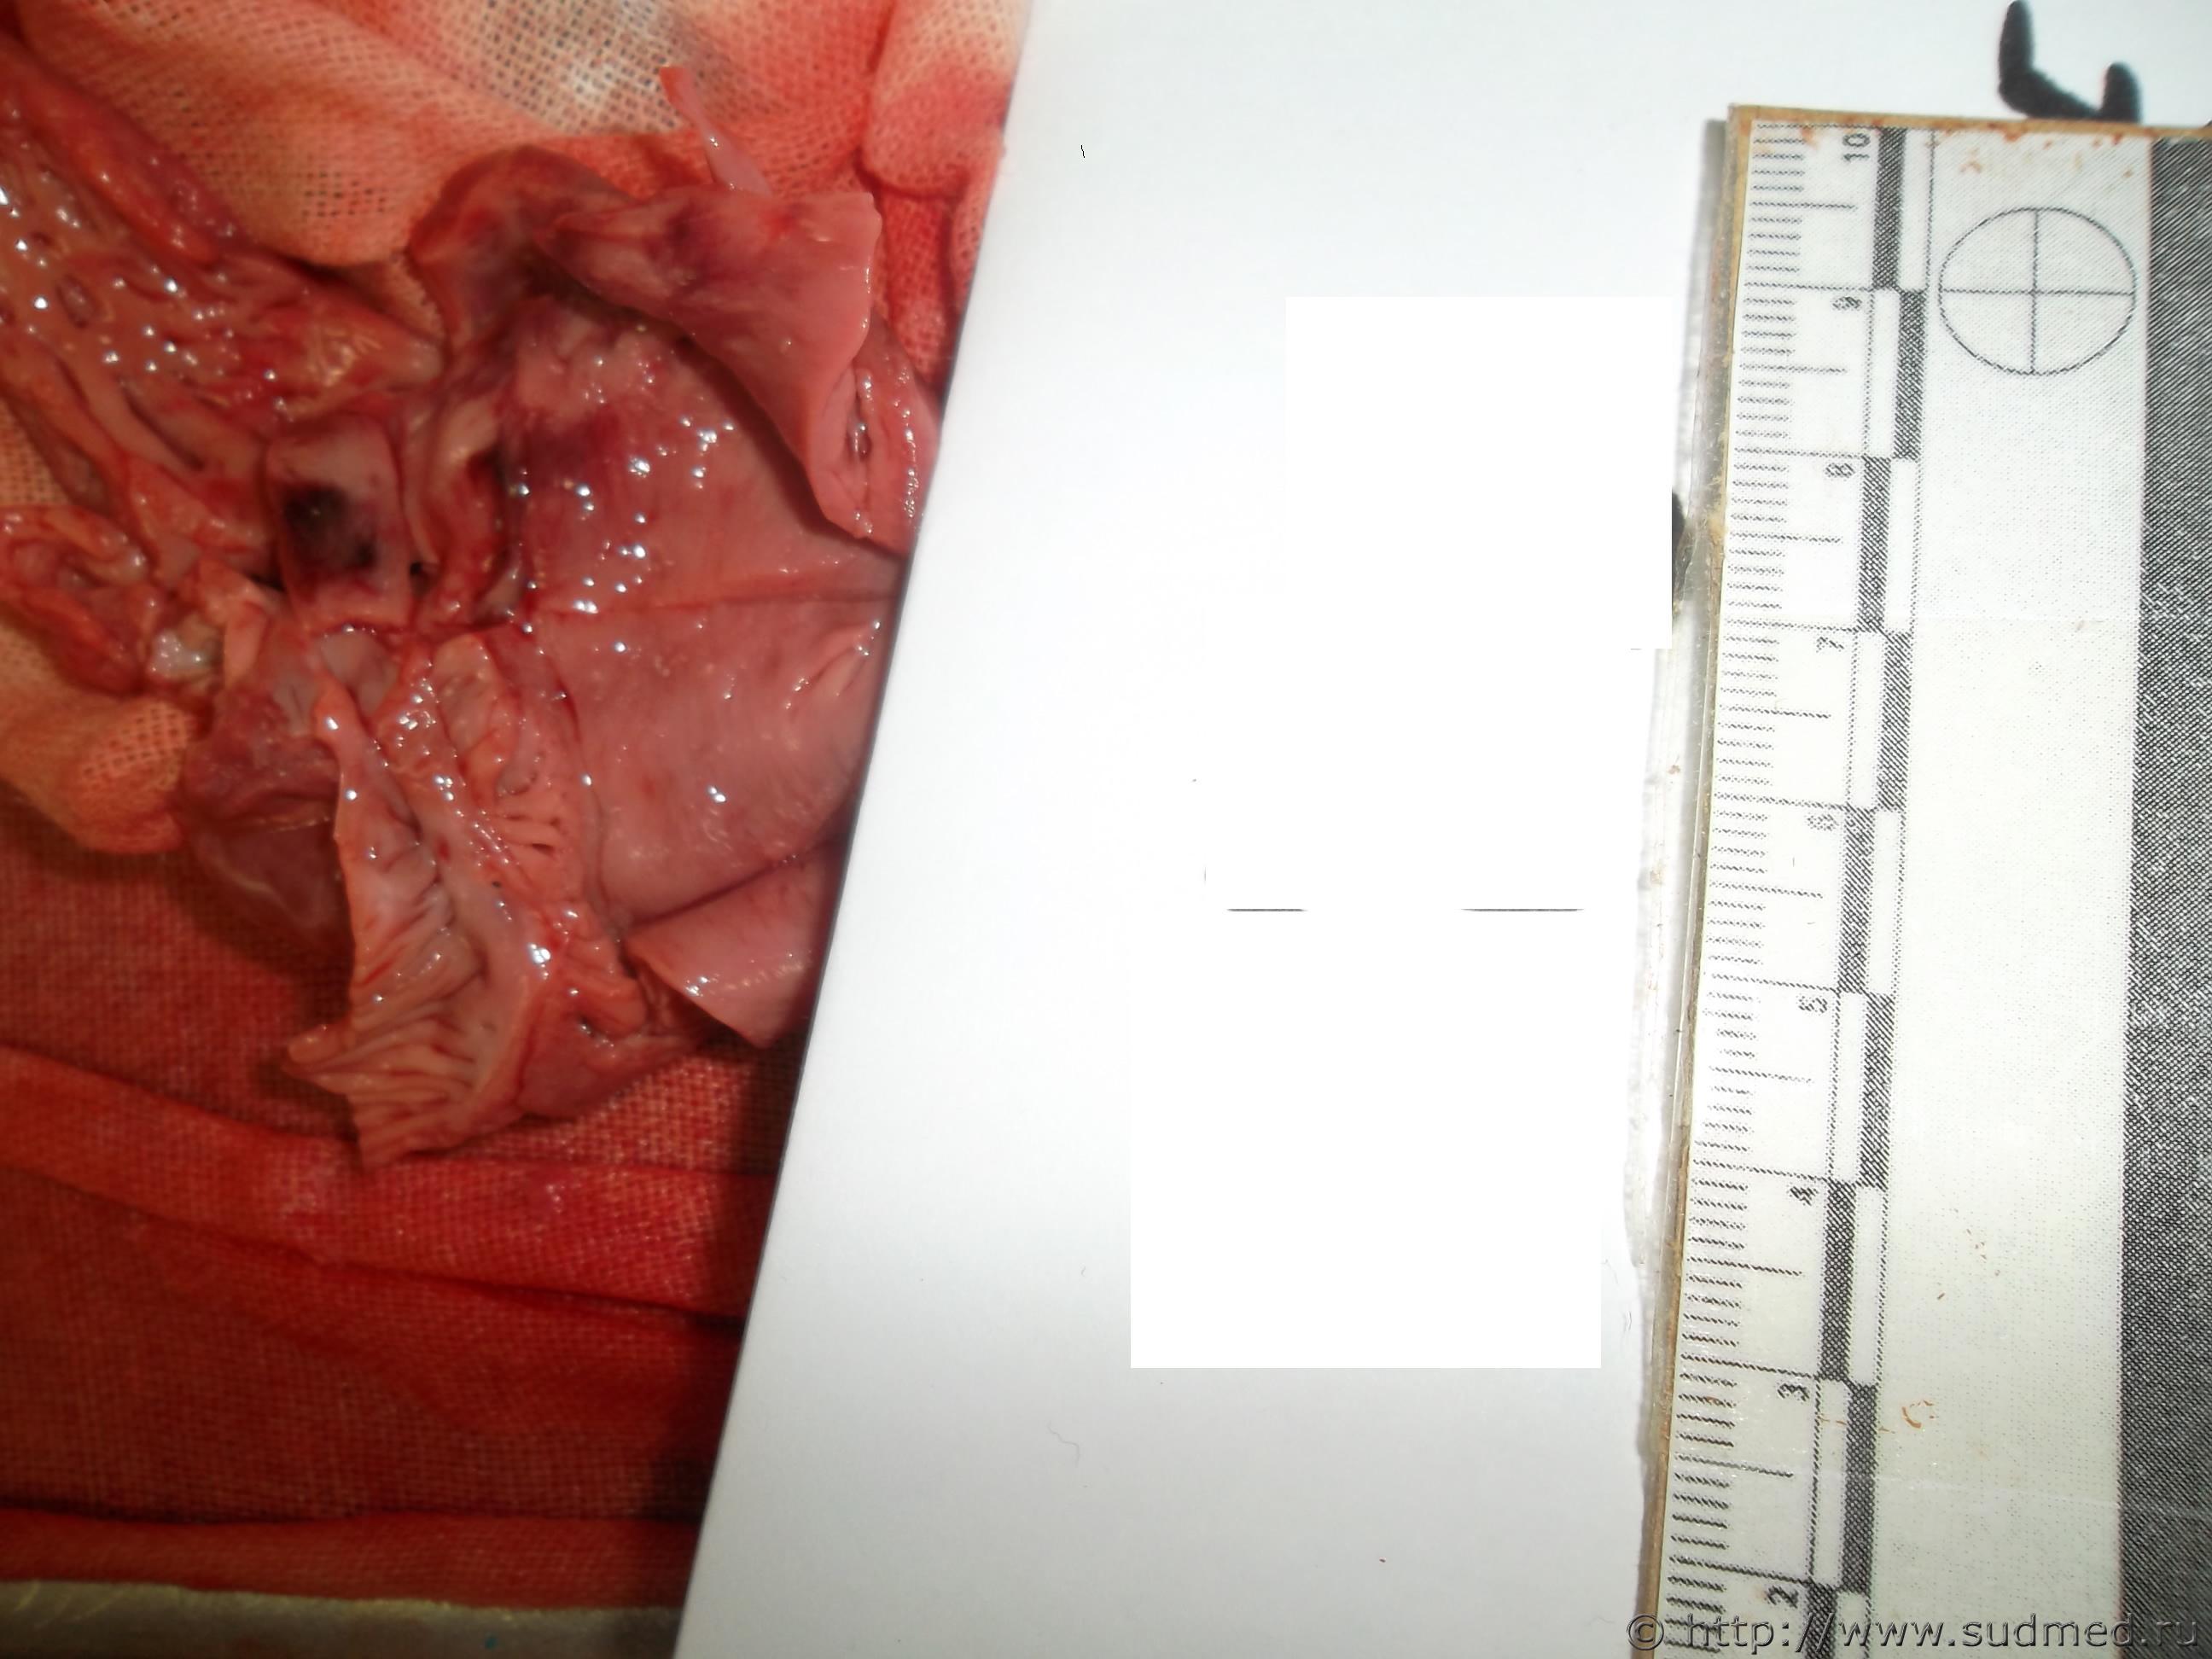

ребенок 5 мес (гистологии пока нет)

Эскизы прикрепленных изображений

Плоховато вижу.Это интрамуральное или же субэндокардиальное кровоизлияние? Вроде вижу и то и другое.Есть ли кровоизлияния в др.органах,слизистых и серозных оболочках? Обстоятельства дела?

А что даст гистология? В данном случае только,то что имеет место инфильтрирующее кровоизлияние?Гляньте на миокард вне кровоизлияний,что там есть за инфаркт?

К сожалению случай не мой, просто не мог пройти мимо - впервые вижу у ребенка. Кровоизлияния есть под плеврой (множественные), из анамнеза - в марте перенесла операцию по лигированию аортального протока; кроме этого при вскрытии обращает на себя внимание только плотноватые включения овальной и округлой формы в ткани легких до 0,5х0,5см (бронхо-легочная дисплазия), ребенок родился массой 820 гр, незаращение овального окна и боталлового протока)

Вот с МВПР надо и начинать,а все кровооизлияния,включая и это - в осложнения,вероятно, здесь ДВС-синдром.

Не каждое кровоизлияние в ткани сердца - инфаркт. Учитывая, что были и субплевральные кровоизлияния, а вероятнее всего и еще где нибудь, то речь идет о проявлении какой либо системной патологии (ДВС к примеру). А вот что к этому привело - надо разбираться. Я последний раз нечто подобное при менингококковой инфекции видел.